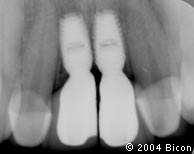

3. | 术前的X光片。 |